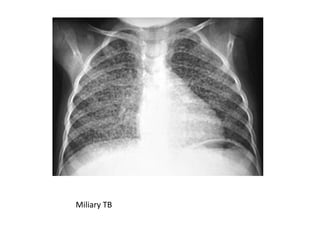

Milliary shadows : Multiple small shadows 2-4mm in diameter

Miliary TB

• Nodular lesionscould be classified as 1. solitary pulmonary nodules 2. Multiple pulmonary nodules • Solitary nodule is defined as an x-ray density completely surrounded by normal aerated lung with circumscribed margins of any shape usually 1- 6cm in greatest diameter. • If its <3cm → ‘Coin lessions’ • If > 3cm → masses Cannon ball lesions:Multiple nodules, widely disseminated,usually multiple, clearly demarcated 1- 2cm in diameter circular shadows throughout the lung fields (characteristic of secondary deposits) Milliary shadows : Multiple small shadows 2-4mm in diameter